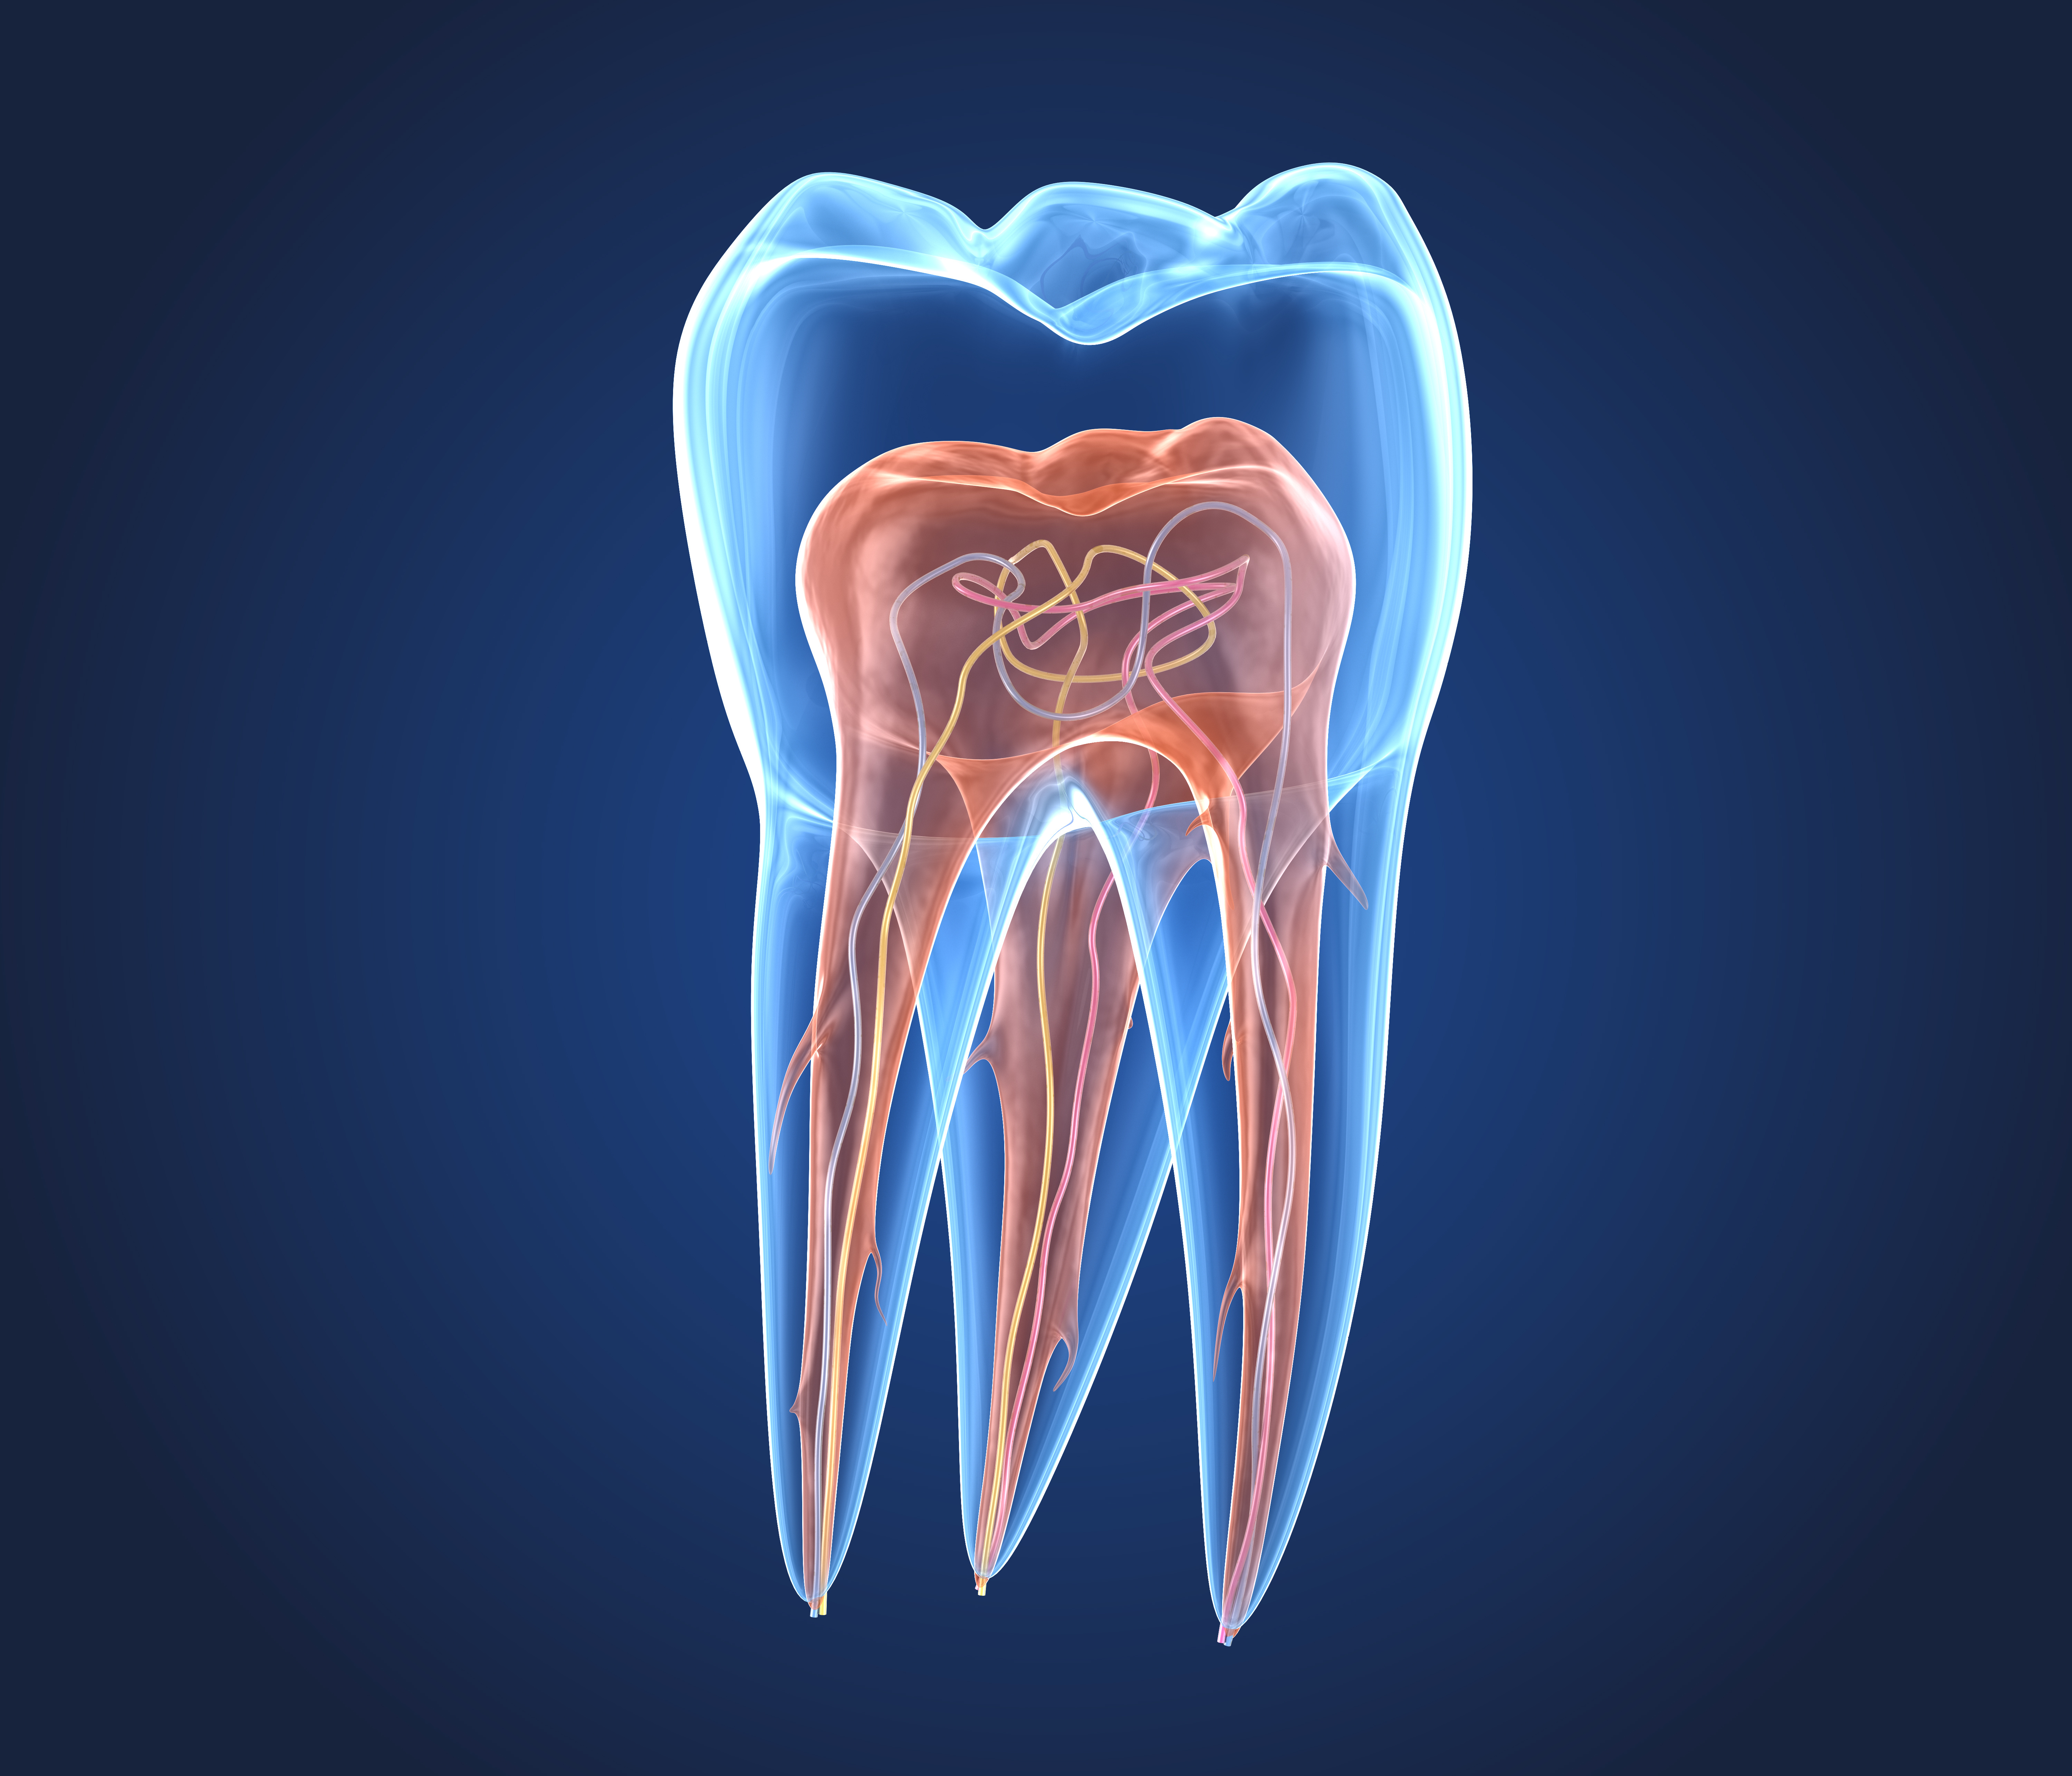

Materials used in filling the root canal, for instance, should not shrink as they harden, should form an airtight bond with the dental material, and should be visible in x-rays. The material used to rebuild the tooth, on the other hand, should have the same properties as the tooth itself.

"Hybrid materials are well-suited to these requirements," said Wolter. "For instance, they only shrink by about 1.3% as they harden, while standard materials generally shrink by 2% to 4%. ORMOCERs can also be adapted to adhere to the different parts of the tooth."